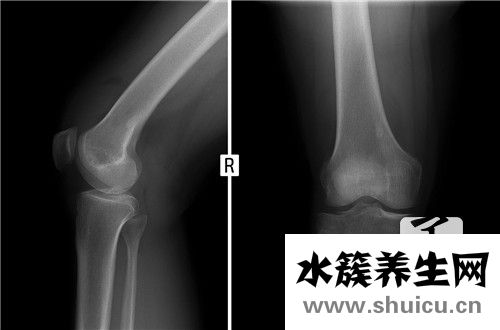

股骨頸骨折是一種常見的骨折,也是多人股骨頭受傷后發(fā)生的疾病。股骨頸骨折如果治療可以多種方式進(jìn)行,手術(shù)方式是更為直接合理的方法。另外,如果損傷不嚴(yán)重,可以按照保守治療。下面,我們將詳細(xì)說明股骨頸骨折 治療。

股骨頭的血液供應(yīng)關(guān)鍵借助骨股的血管,一旦股骨頸骨折,非常容易導(dǎo)致股骨頭的腦缺血壞死,因此股骨頸骨折一般挑選合閉復(fù)位,三根釘,內(nèi)固定不動手術(shù)治療或是髖關(guān)節(jié)置換手術(shù)治療,假如股骨頸骨折挪動不顯著,骨折比較平穩(wěn),嵌插骨折或是病人的人體標(biāo)準(zhǔn)較弱,不可以承受手術(shù)治療還可以挑選保守治療。

保守治療一般是患側(cè)皮牽引,肯定臥床休息兩月,穿釘子鞋,避免 轉(zhuǎn)動,另外搞好家庭護(hù)理,兩月上下到醫(yī)院門診復(fù)診,掌握骨折的痊愈狀況。

導(dǎo)致老人產(chǎn)生骨折有兩個基本要素,骨質(zhì)疏松骨抗壓強(qiáng)度降低,加上骨股上區(qū)滋潤血管孔滿布,均可使骨股運(yùn)動生理學(xué)構(gòu)造消弱,使骨股敏感。此外,因老人髖周肌群退行性變,遲鈍,不可以合理地相抵髖骨危害地應(yīng)力,加上髖骨遭受地應(yīng)力很大(休重2~6倍),部分地應(yīng)力紛繁復(fù)雜,因而不需要多少的暴力行為,如平地上摔倒、由床邊跌下或下肢忽然扭曲,乃至在無顯著創(chuàng)傷的狀況下都能夠 產(chǎn)生骨折。而青年人股骨頸骨折,通常因?yàn)楸容^嚴(yán)重?fù)p害如車禍?zhǔn)鹿驶蚋呖諌嬄渲職垺R蜻^多太久負(fù)重勞動者或走動,慢慢產(chǎn)生骨折者,稱作疲憊骨折。

股骨頸骨折的最好治療方法是技巧復(fù)位內(nèi)固定不動,要是有令人滿意復(fù)位,大部分內(nèi)固定不動方式均可得到 80%~90%的痊愈率,不痊愈病案今后需手術(shù)治療解決亦僅5%~10%,即便產(chǎn)生股骨頭壞死,亦僅1/3病案需手術(shù)醫(yī)治。因而股骨頸骨折的醫(yī)治標(biāo)準(zhǔn)應(yīng)是:初期無創(chuàng)性復(fù)位,有效幾枚釘固定不動,初期康復(fù)治療。人工服務(wù)膝關(guān)節(jié)鏡只融入于65歲以上,GardenⅢ、Ⅳ型骨折且能承受手術(shù)治療麻醉及外傷的傷員。

復(fù)位內(nèi)固定不動方式的結(jié)果,除與骨折損害水平,如挪動水平、破碎水平和血運(yùn)毀壞是否相關(guān)外,關(guān)鍵與復(fù)位恰當(dāng)是否、固定不動恰當(dāng)是否、術(shù)后恢復(fù)狀況相關(guān)。